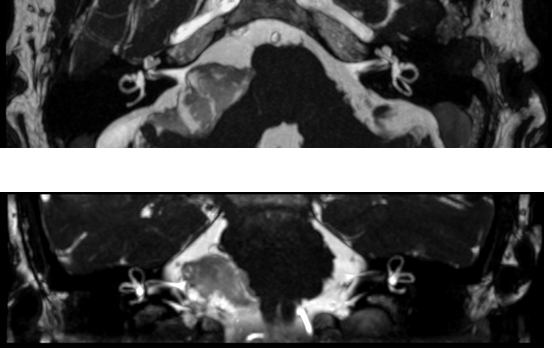

西门子MAGNETOM Aera 纪元四度磁共振可进行神经系统、脊柱、四肢关节、腹部、心脏、血管等全身各个系统的不同疾病的检查,而且能进行波谱分析,对肿瘤的性质鉴定有很高临床价值。对CT无法发现的超早期脑梗塞病变具有无可替代的作用,能发现发病后几分钟内的病灶,为挽救患者生命和改善预后、减少致残率赢得时间。

CASE 3: 胸椎肿瘤(金属植入物)